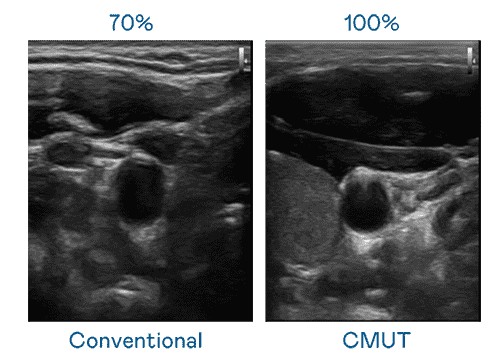

CMUT 技术是一种用电容式微机电元件来产生超音波讯号的技术。。。。与传统 PZT 压电式技术相比,,,CMUT 频宽增加 30%,,,更宽频的超音波讯号让影像解析度大幅提升,,是实现高影像品质医疗超音波扫描、、、、促进精准医疗发展的关键技术。。

大频宽带来超清晰影像

超音波影像的解析度高低,,,,首先取决于探头能发出的讯号频宽。。z6mg·人生就是博 CMUT 可提供高清晰的超音波讯号,,,提供高频宽、、高灵敏度、、、、影像纹理细节更高的超音波影像,,,,协助医护人员缩短影像判读时间及利用精准的医疗影像进行诊断。。